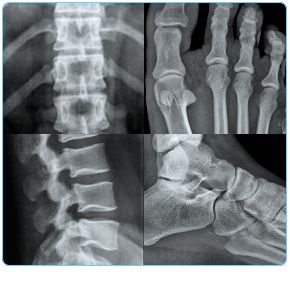

Bio2 Technologies has developed bone graft substitute products for the fast-growing markets of spine and foot and ankle surgery:

- Product pipeline targets two high growth product categories in orthopedics, spine and foot and ankle surgery.